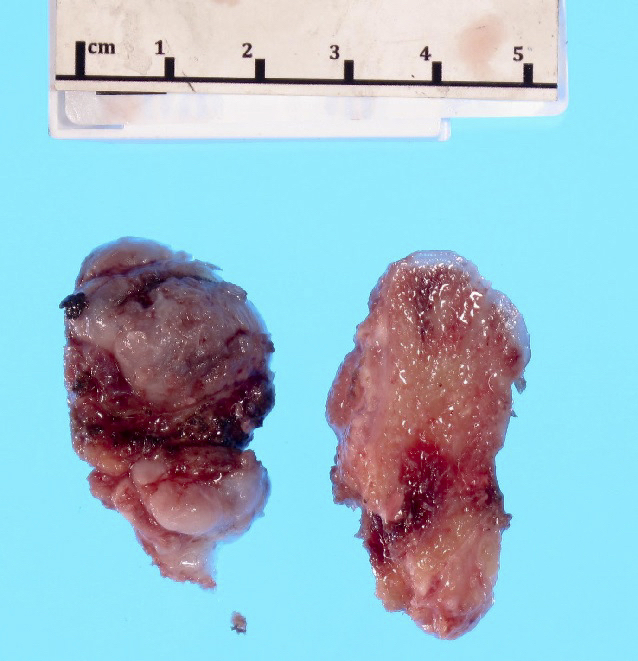

Gross description

- Pedunculated or sessile bony lesion with hyaline cartilage cap

Gross images